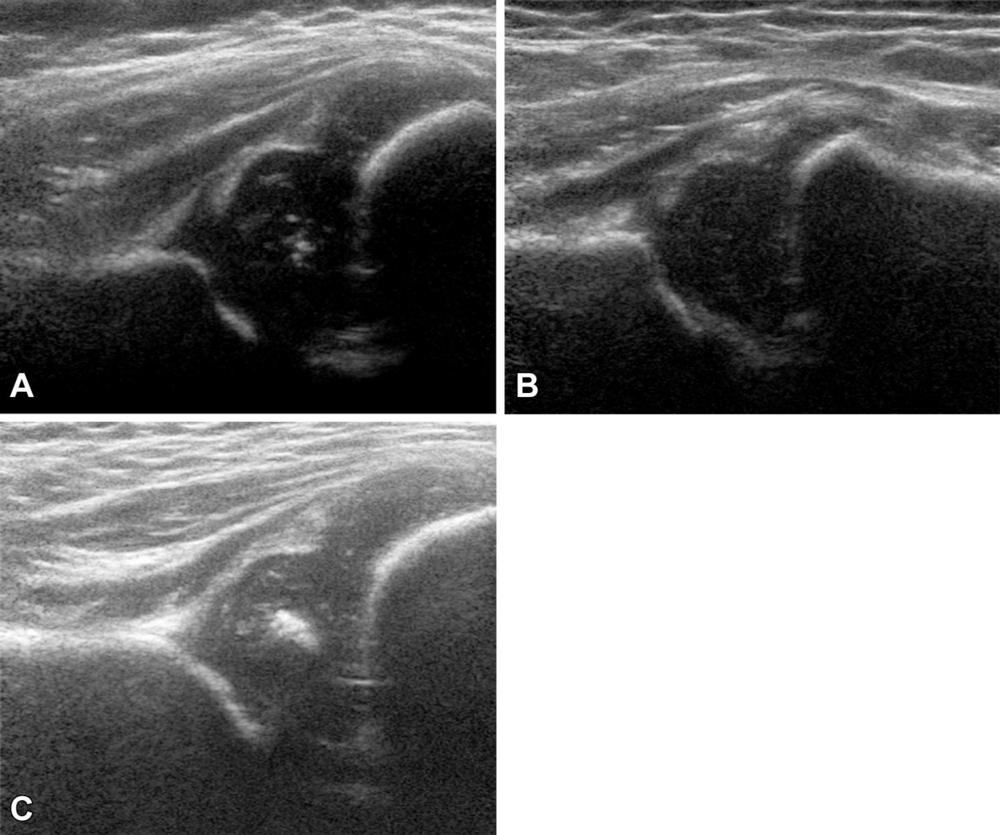

Figure 4. Examples of hip US images obtained with mode 1; no contrast material was used. The presented hips were (A) −1.58 (girl), (B) +0.11 (girl), and (C) +1.80 (boy) standard deviations from the mean shape.

High-res (TIF) version